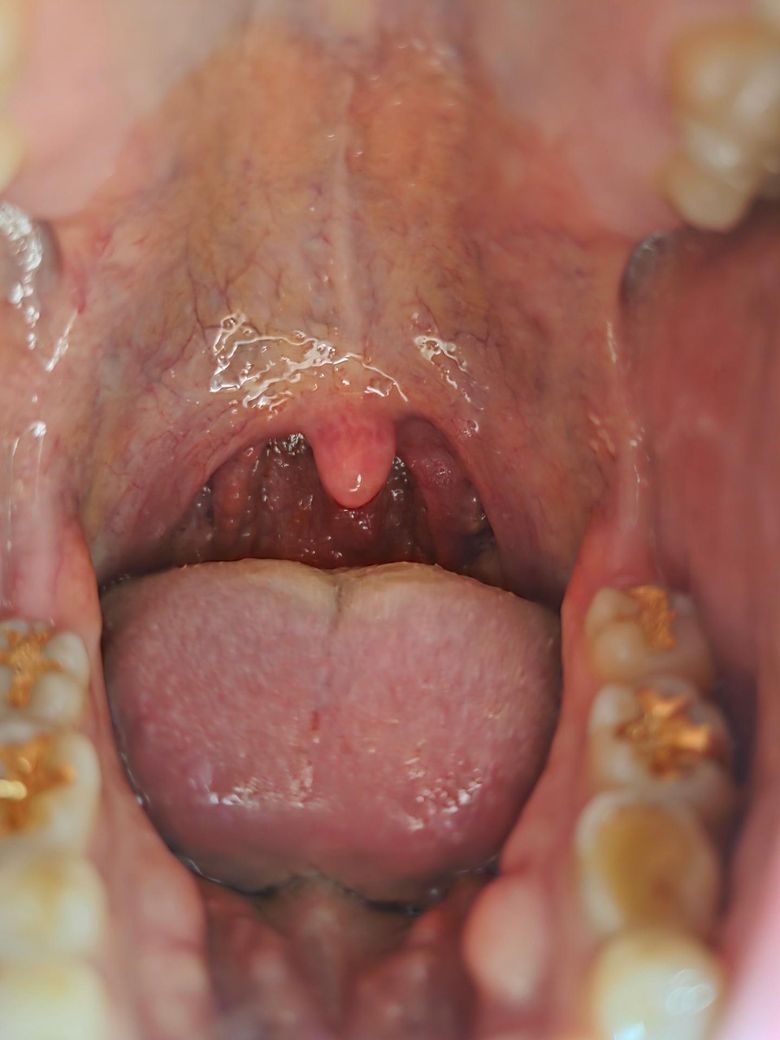

• 2번 째 사진

1.육안으로 보기에는 뚜렷한 감염의 징후는 보이지 않는 것 같습니다.

목이 붓고 통증이 느껴진다면 인후염이나 편도선염일 가능성이 높습니다.

고열이 나고 침 삼키기가 힘들며 하얀 반점이 보인다면 세균성 감염을 의심해야 해요.